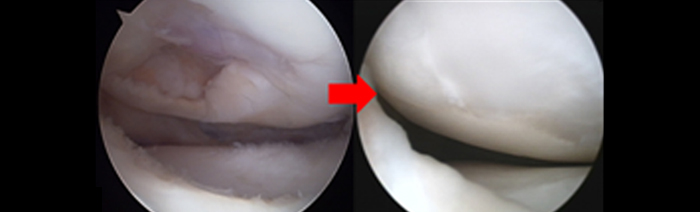

1. 분야별 전문 과장의 특성화 진료 좋은삼선병원 인공관절센터는 고관절, 무릎 관절, 어깨 관절, 수족부 관절 등 질환 부위별 특성화 진료를 통해 맞춤 치료를 시행합니다.

2. 인공관절시술 시행 병원(고관절 / 슬관절 / 견관절)좋은삼선병원 인공관절센터는 고관절, 슬관절, 견관절 등 다양한 인공관절시술을 시행하고 있습니다.